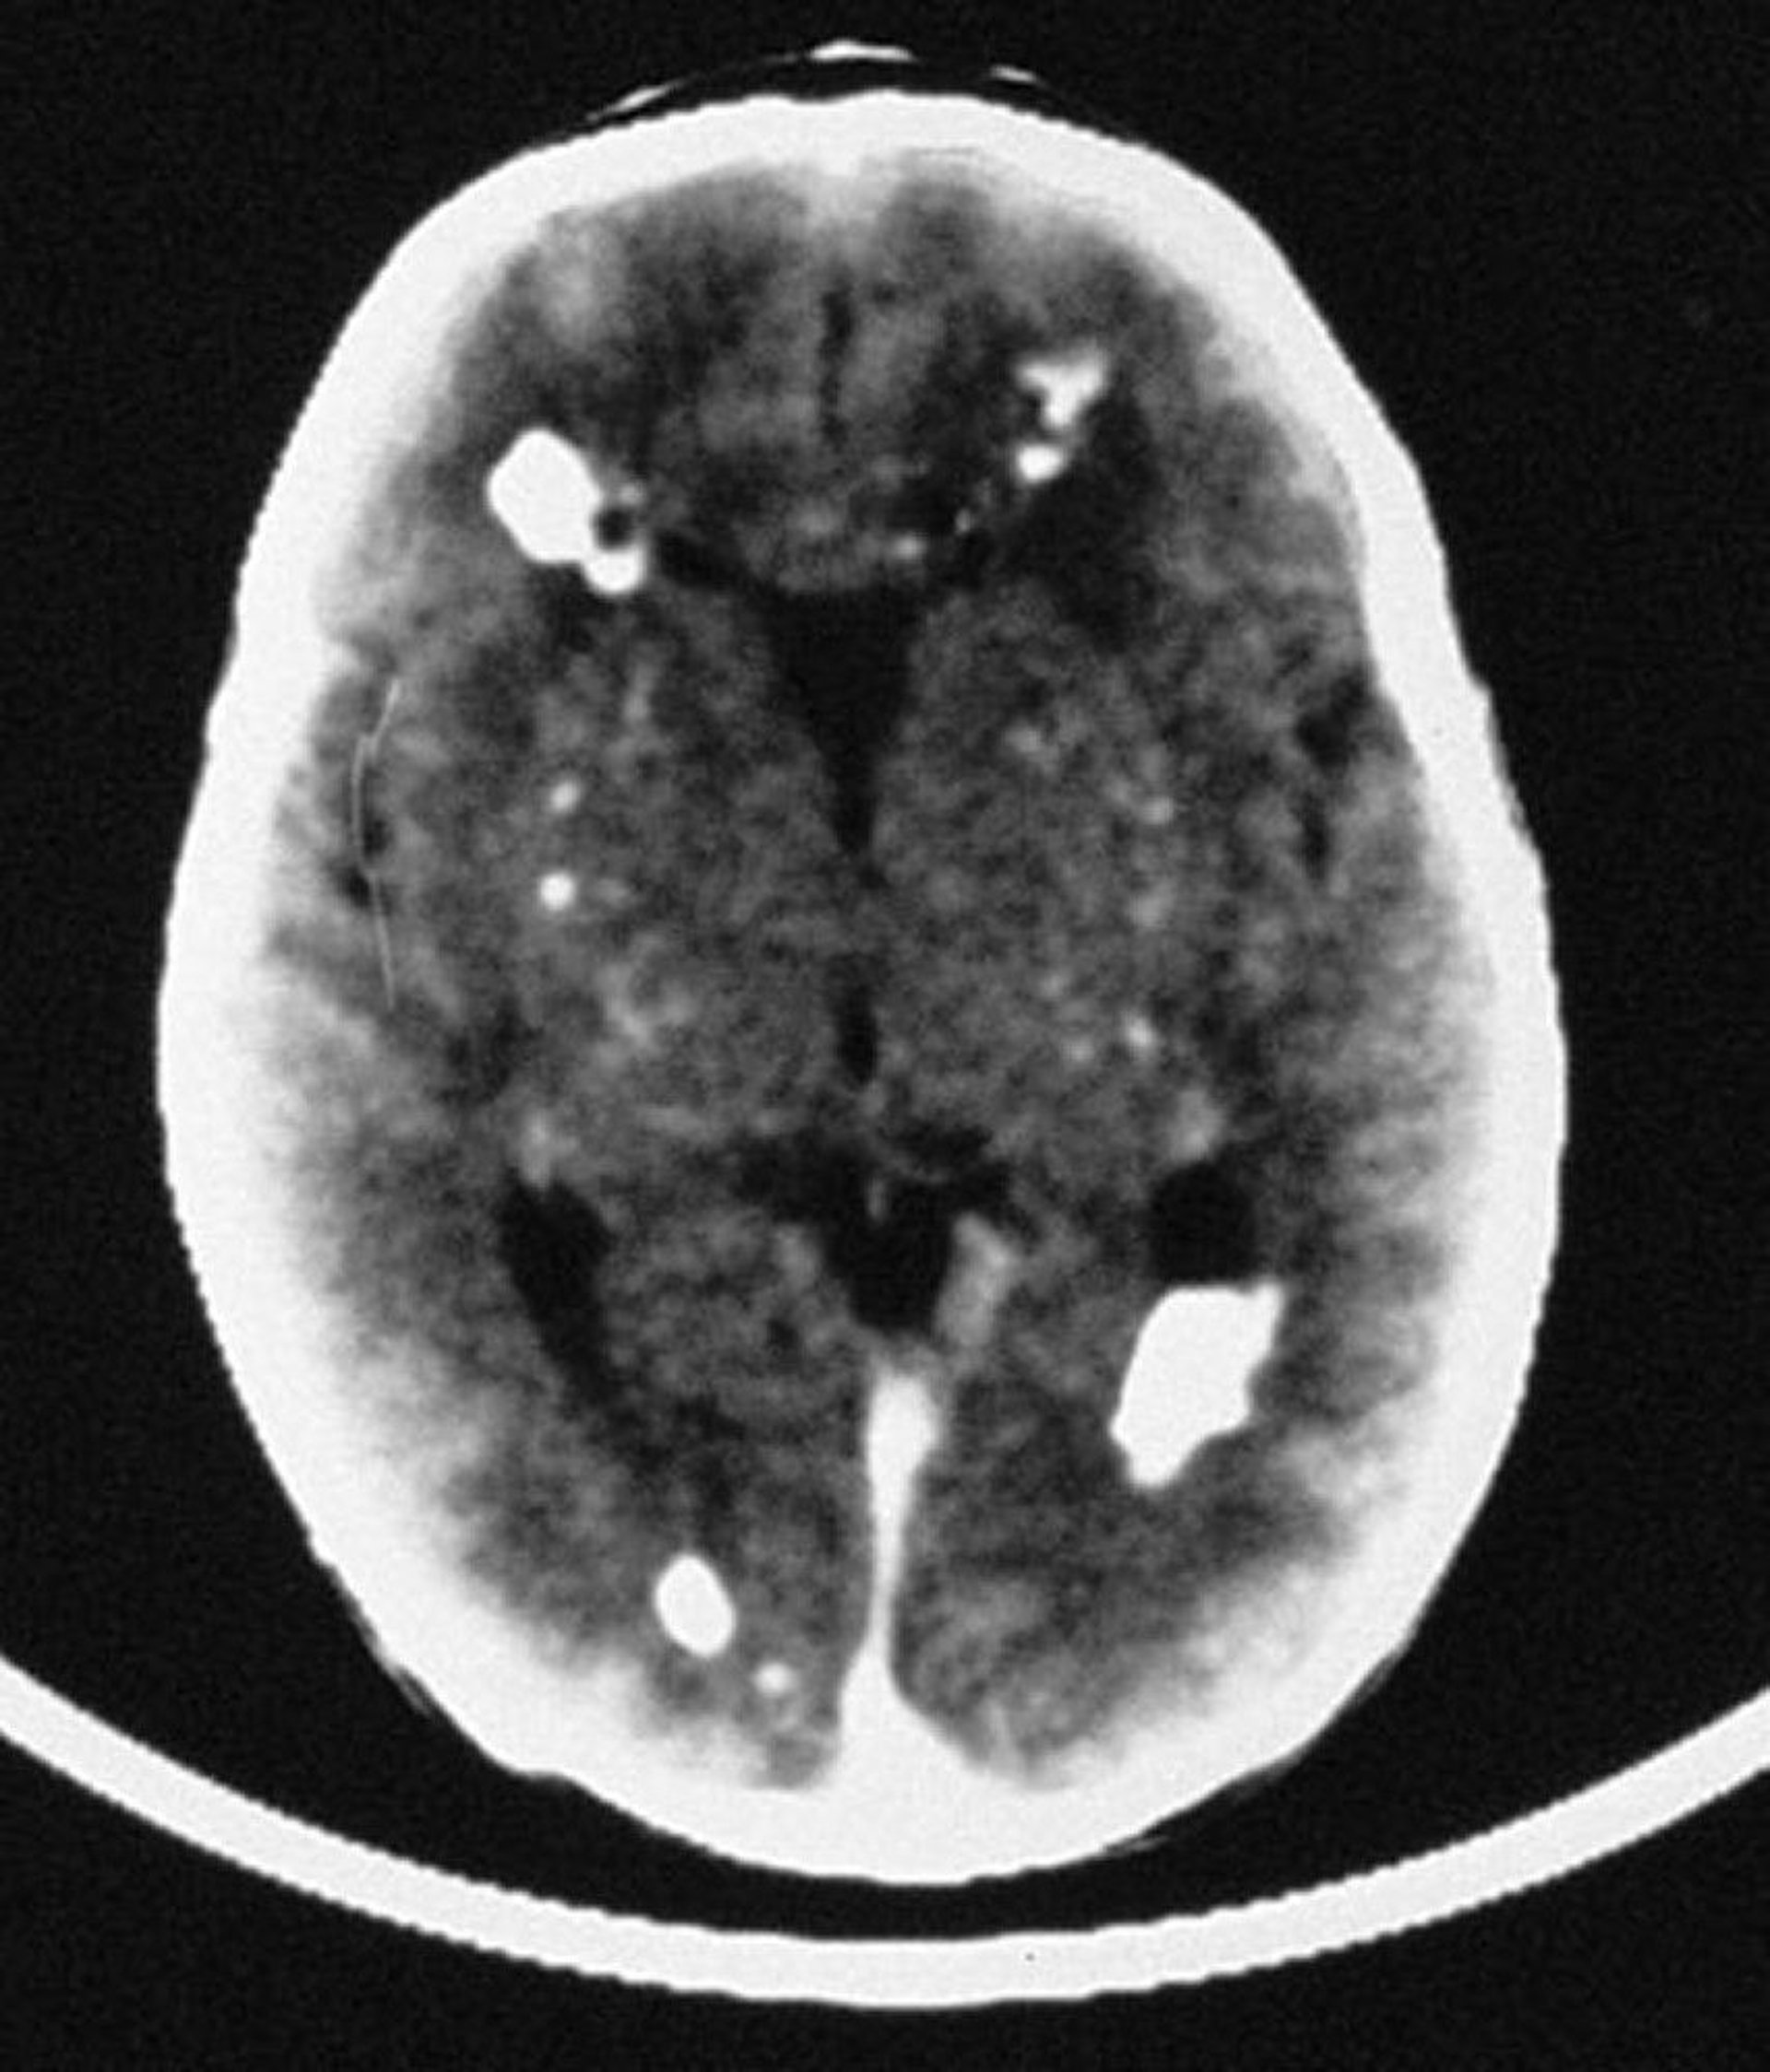

Congenital Cytomegalovirus Infection

In this image, the CT scan reveals multiple intracranial calcifications, mostly periventricular in distribution, but also involving vascular structures of the brain.

By permission of the publisher. From Demmler G: Congenital and perinatal infections. In Atlas of Infectious Diseases: Pediatric Infectious Diseases. Edited by CM Wilfert. Philadelphia, Current Medicine, 1998.